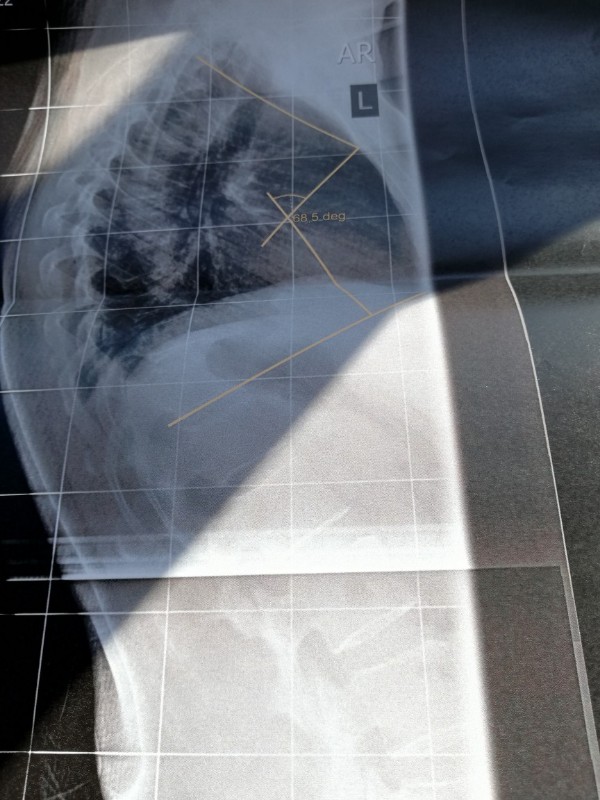

- IMG_20190329_114551-864x1152-600x800.jpg (127.7 KiB) 8584 mal betrachtet

- IMG_20190329_114843-864x1152-600x800.jpg (101.8 KiB) 8584 mal betrachtet

Nachdem ich gestern bei Dr. AL Alwan in Bottrop war, bin ich heute direkt in Oberhausen zum Röntgen der seitlichen Wirbelsäule gefahren. Dr. Al Alwan ist der Ansicht meine Beschwerden könnten von einer Kyphose kommen. Ich bin 54 Jahre alt und habe seit ca 2 Jahren teilweise unerträgliche Schmerzen. Meine Hausärztin ist der Meinung die Schmerzen sind somatoform und mein bisheriger Orthopäde löst mir regelmäßig Blockaden und rät mir zu Sport und Yoga. Leider werden die Schmerzen dadurch schlimmer. Ein MRT 2018 ergab eine leichte Skoliose und eine leichte Kyphose. Leider konnte ich heute mit keinem Arzt über das Röntgenbild sprechen. Es sind Winkel mit 68,5 deg eingezeichnet. Sagt das jemanden was? Es steht nichts von Cobb o. ä. dabei. Ich bin ziemlich ratlos ob das die Ursache der Schmerzen sein könnte. Freue mich über jede Erfahrung oder Tipp von euch. Falls es klappt lade ich mal 2 Bilder hoch. LG und ein schönes, sonniges Wochenende

68,5 Grad könnte sich auf die Hyperkpyhose beziehen, eine normale BWS Kyphose liegt im Bereich 25-40 Grad.

Dr. AL Alwan war nach der Untersuchung der Meinung, dass die Skoliose nicht sonderlich ausgeprägt wäre und mein Rücken sichtbar rund sei. Deshalb die Überweisung zum Röntgen um die Kyphose zu vermessen. Allerdings wurde nur eine seitliche Aufnahme der gesamten Wirbelsäule gemacht. Den Ausdruck und eine CD vom BWS - MRT von 2018 habe ich in seinen Briefkasten geworfen, ich denke nächste Woche weiß ich mehr. Mir ist nur nicht klar ob die 68,5 ged mit Cobb gleichzusetzen sind